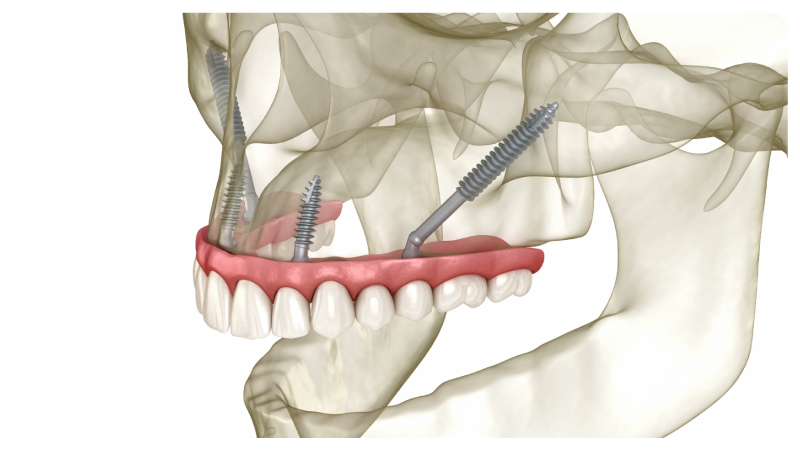

Implantes Cigomáticos:

Solución para Pérdida Ósea

Si el paciente tiene una gran reabsorción ósea en el maxilar superior, los implantes cigomáticos ofrecen una solución efectiva al anclarse en el hueso malar (pómulos).